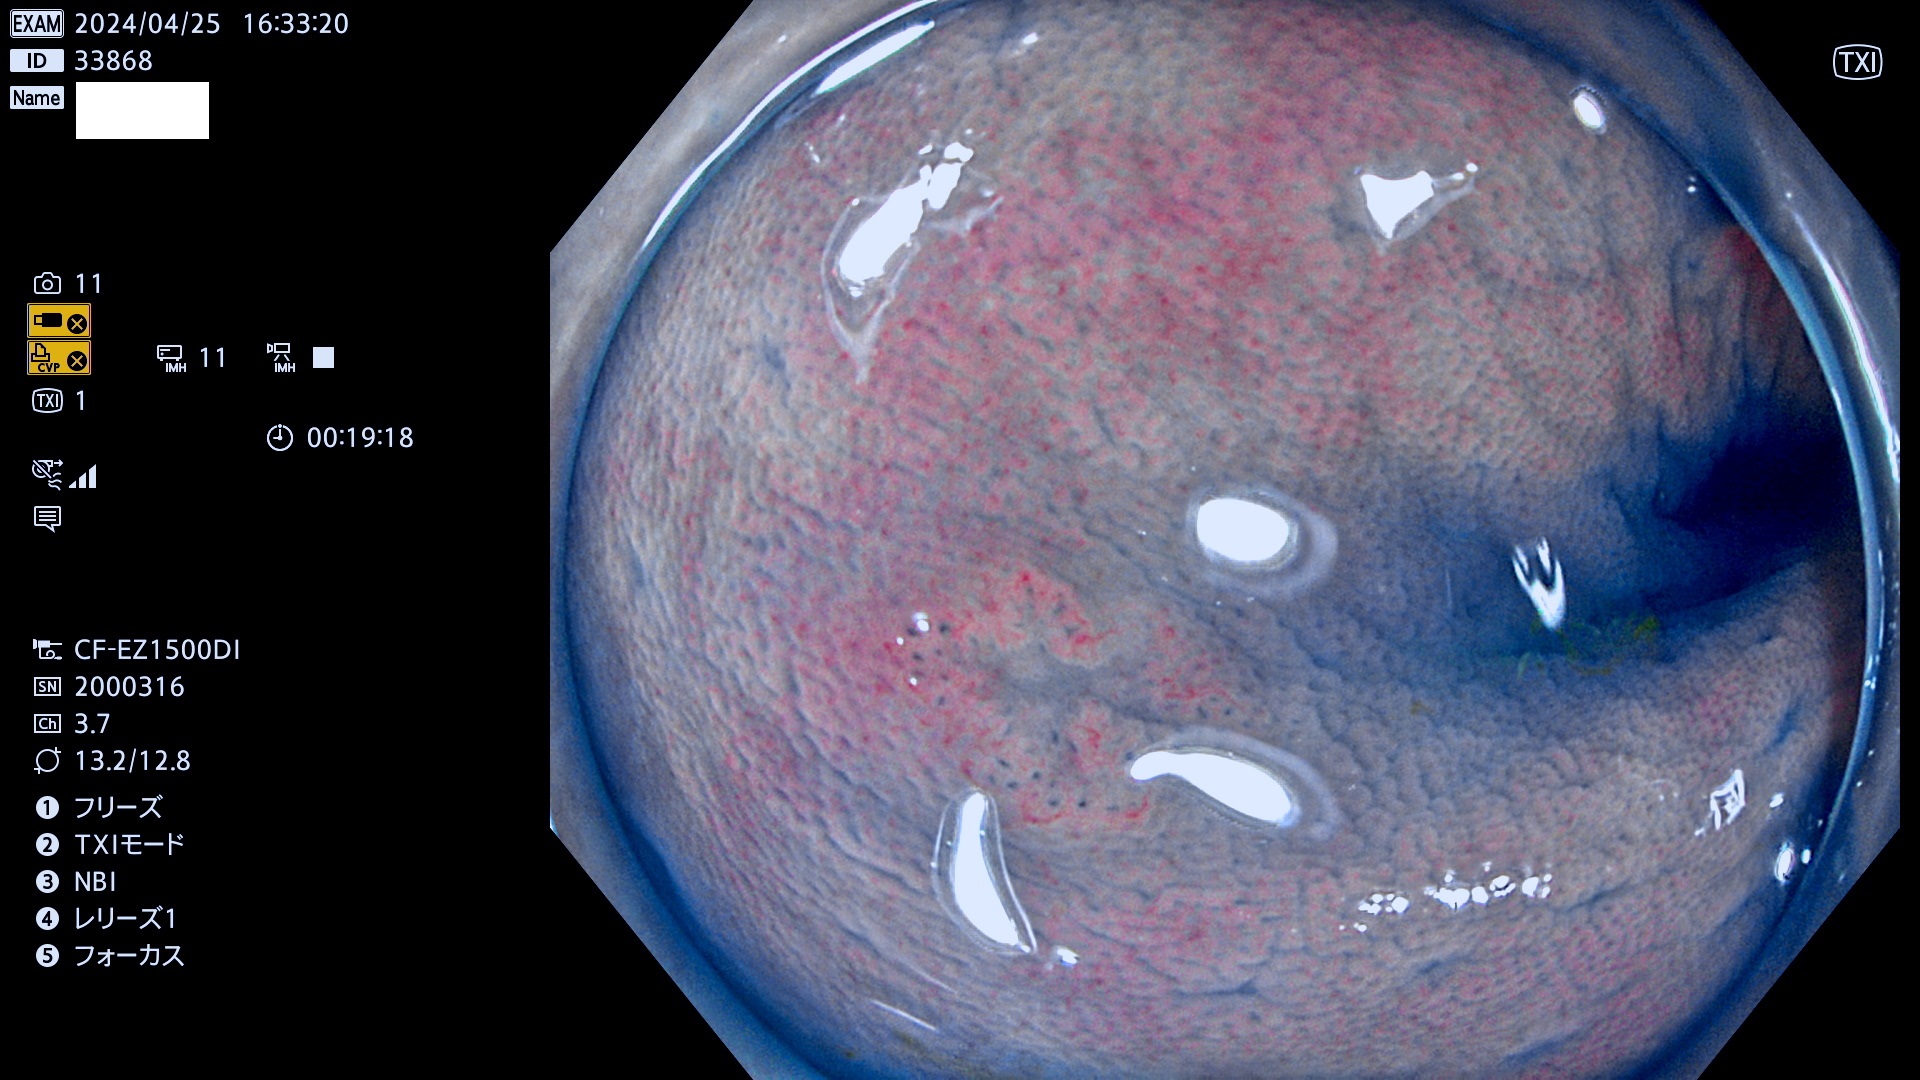

表面型腺腫(Flat Adenoma)の中で、完全に平坦な物をUb、陥凹している物をUcと呼びます。平坦隆起型(Ua)よりも、発見が難しく危険な病変です。

抽出の対象期間 2024年4月25日〜4月29の5日間(50件の検査)7件 (7/50=14%)